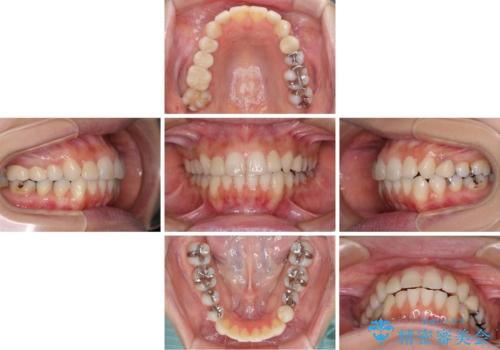

- 前歯のデコボコと矮小歯、更には痛みを感じる奥歯のむし歯を気にして来院された患者様です。

奥歯には根管治療が必要な歯があり、上顎側切歯は左右ともに矮小歯でした。

上下前歯のデコボコはワイヤーでもインビザラインでも対応可能でしたが、補綴治療が多く必要となることから、インビザラインでの矯正治療を行いながら、並行して補綴治療を行うこととしました。

まずは根管治療を行った上で矯正治療用の仮歯を装着し、矯正治療後半に補綴治療を並行して行うこととしました。